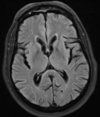

Esclerose mesial temporal

Atrofia hipocampal e hipersinal T2. Cerca de 10% dos casos são bilaterais (dificulta o diagnóstico). A etiologia é desconhecida, mas há uma relação entre STM e convulsões febris prolongadas no início da vida A esclerose mesial temporal pode ocorrer em associação com outras patologias, principalmente displasia cortical focal (dual pathology).

203